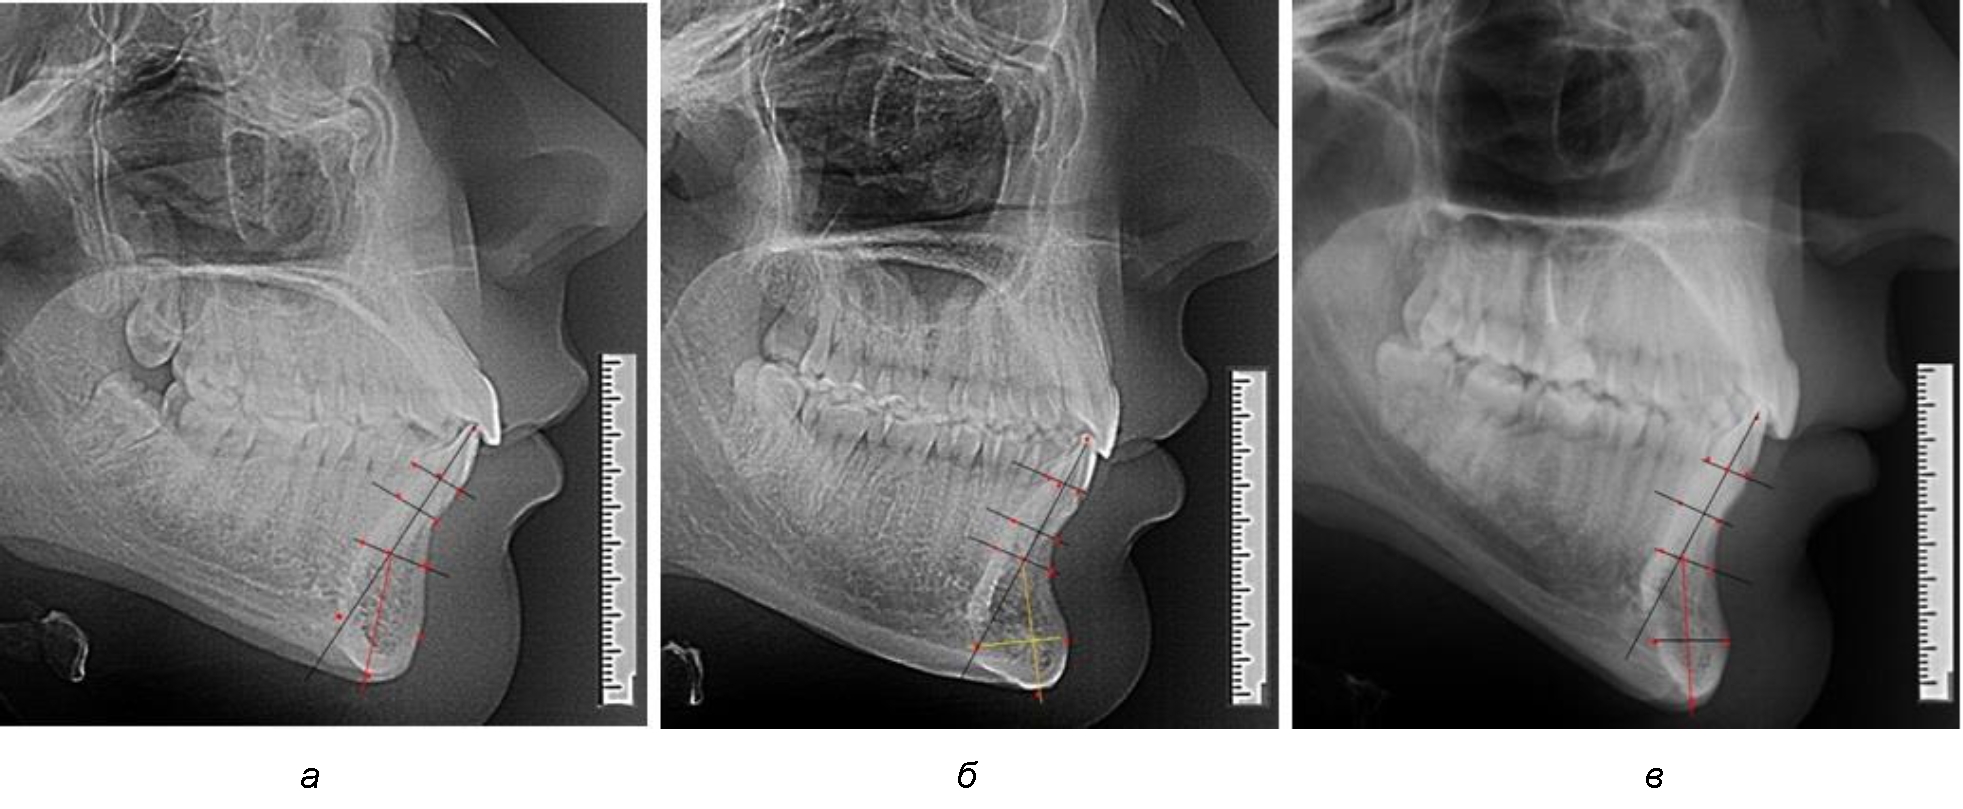

На нижнем контуре подбородочного выступа определяли положение ментальной точки Me. Линия, соединяющая апикальную точку с ментальной, определяла высоту подбородочного выступа тела нижней челюсти. Высота зубочелюстного сегмента IsL–Ме измерялась от резцовой до подбородочной точки. Вертикальная линия Ap–Me делила подбородочный выступ на две части: переднюю и заднюю (рис. 1).

Рис. 1. Ориентиры для исследования нативных препаратов (а) и рентгенограмм (б) резцового нижнечелюстного сегмента

Сагиттальные размеры зубоальвеолярной части сегмента определялись между точками Bsm и Bsm', в апикальной части сегмента – B и B'. В подбородочной части сегмента из передней выступающей точки подбородка Pog проводили линию перпендикулярно к линии Ар–Ме с определением точки Pog'. Расстояние Pog–Pog' определяло ширину подбородочного выступа.

При анализе полученных данных обращает на себя внимание факт того, что из вертикальных параметров зубоальвеолярной части сегмента наиболее вариабельным является размер между апикальными точками Downs и Schwarz (BSM–B), который составлял (6,79 ± 0,54) мм, при величине сигмального отклонения – 2,35. Также большая ошибка репрезентативности и сигмальное отклонение было отмечено при оценки ширины подбородочного выступа. В связи с этим встречались варианты резцовых сегментов нижней челюсти различные как по ширине, так и по высоте, а также по расхождению положения апикальных точек по Downs и Schwarz (рис. 3).

Рис. 3. Варианты среднего (а), широкого (б) и узкого (в) нижнечелюстного резцового сегмента